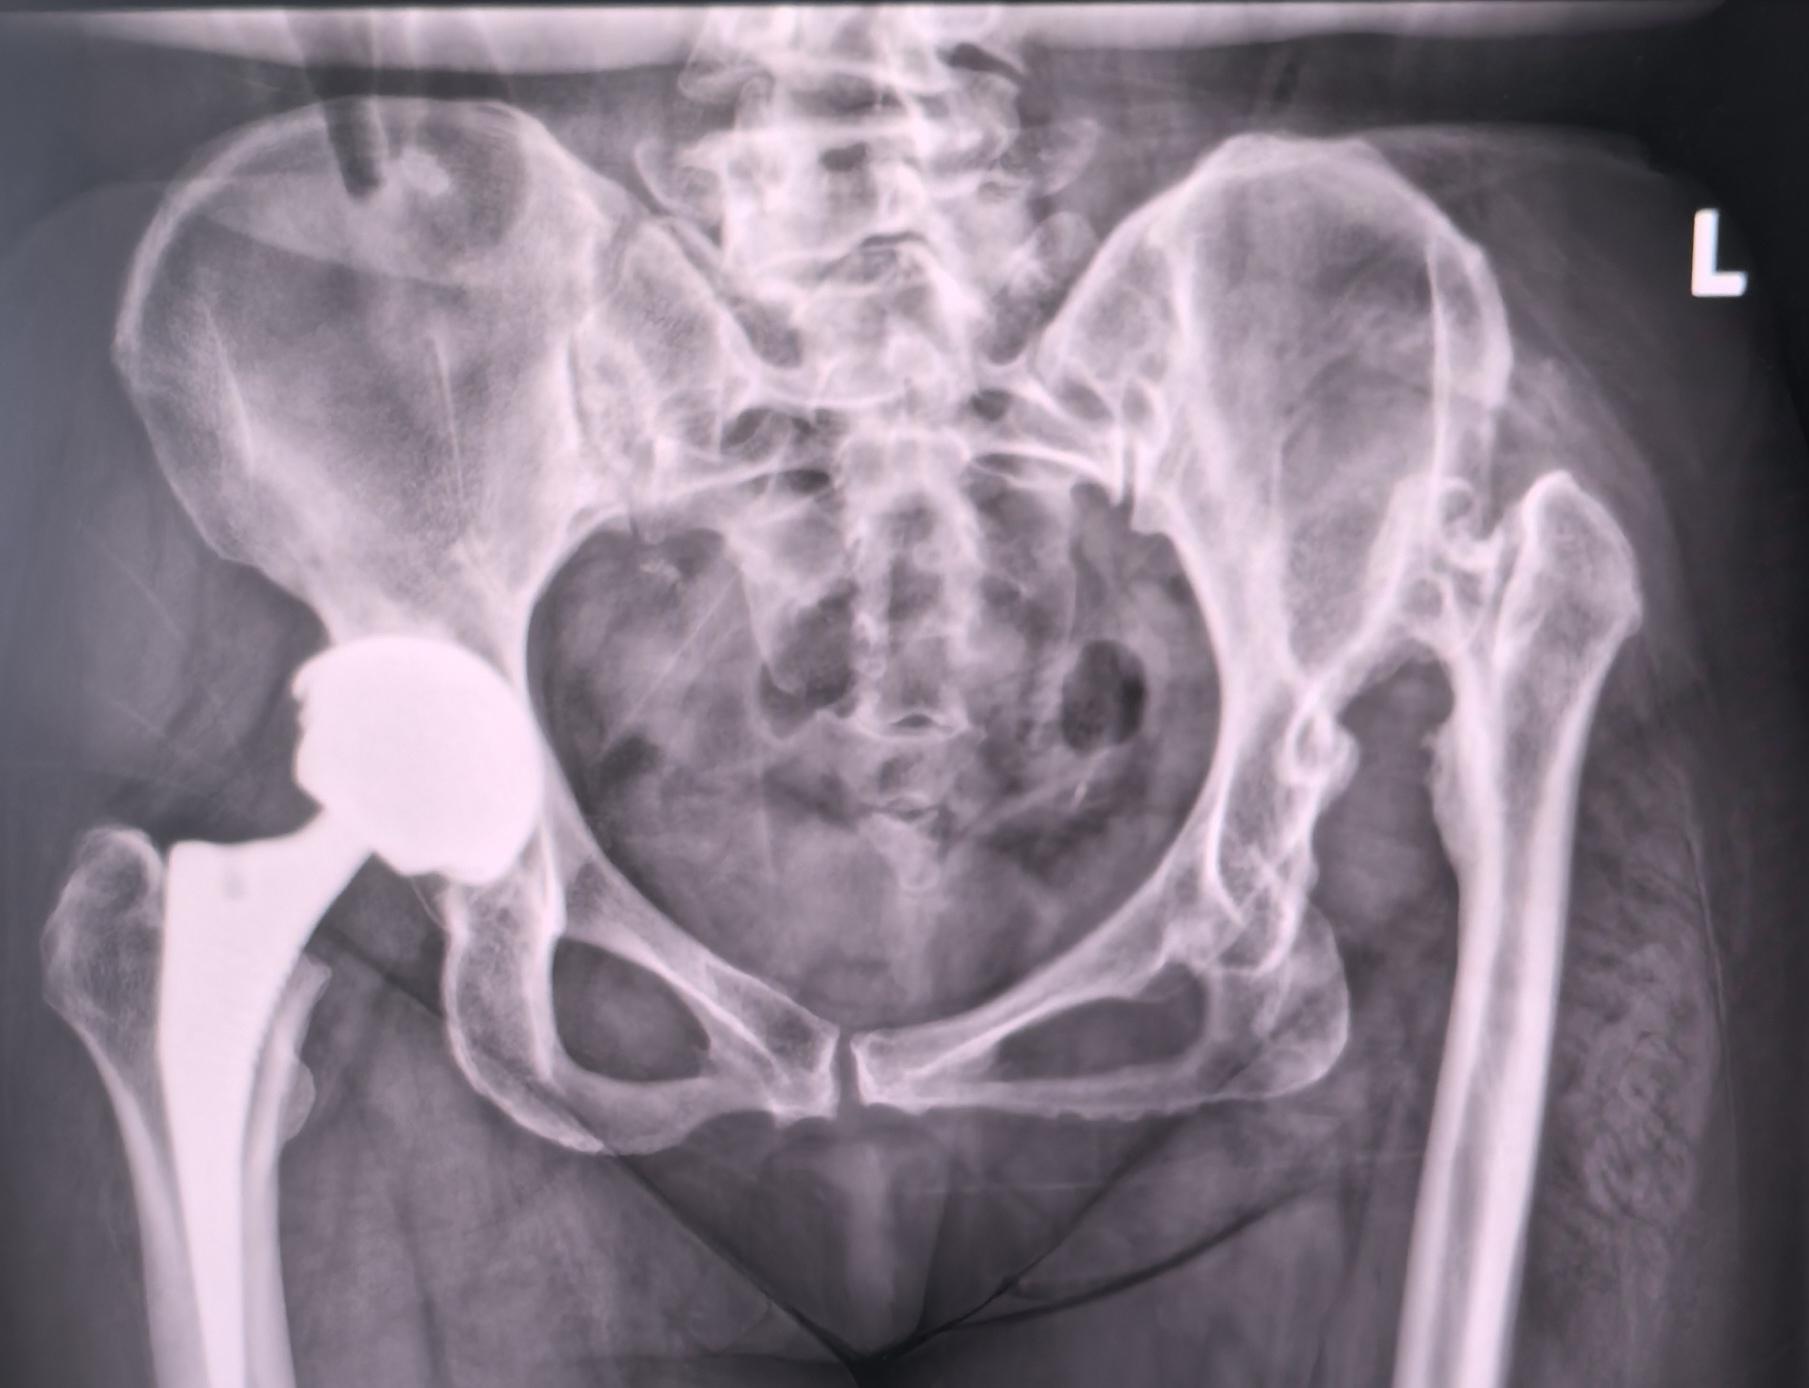

DDH先髋,高难度。DDH Crowe IV型,高难度手术,半个骨盆发育都不好,真臼25mm,髓腔直径5mm,术前患侧短4cm,术后等长,无神经症状,2天拄拐下床行走。愿每一位先髋患者都能得到有效的治疗,早日恢复正常生活🌹